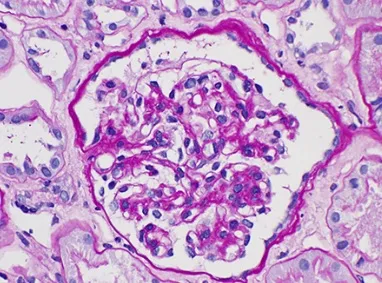

Meu paciente com NIgA tem proteinúria entre 0,5–1,0 g/dia, já está em iECA e iSGLT2: devo pensar em imunossupressão?

Proteinúria entre 0,5–1,0 g/dia na NIgA não é benigna e já se associa a maior risco de progressão renal. A evidência atual reforça <0,5 g/dia como alvo terapêutico, valorizando proteinúria cumulativa e tendência ao longo do tempo. Antes de pensar em imunossupressão, o foco deve ser otimização máxima da terapia de suporte e estratificação cuidadosa de risco.